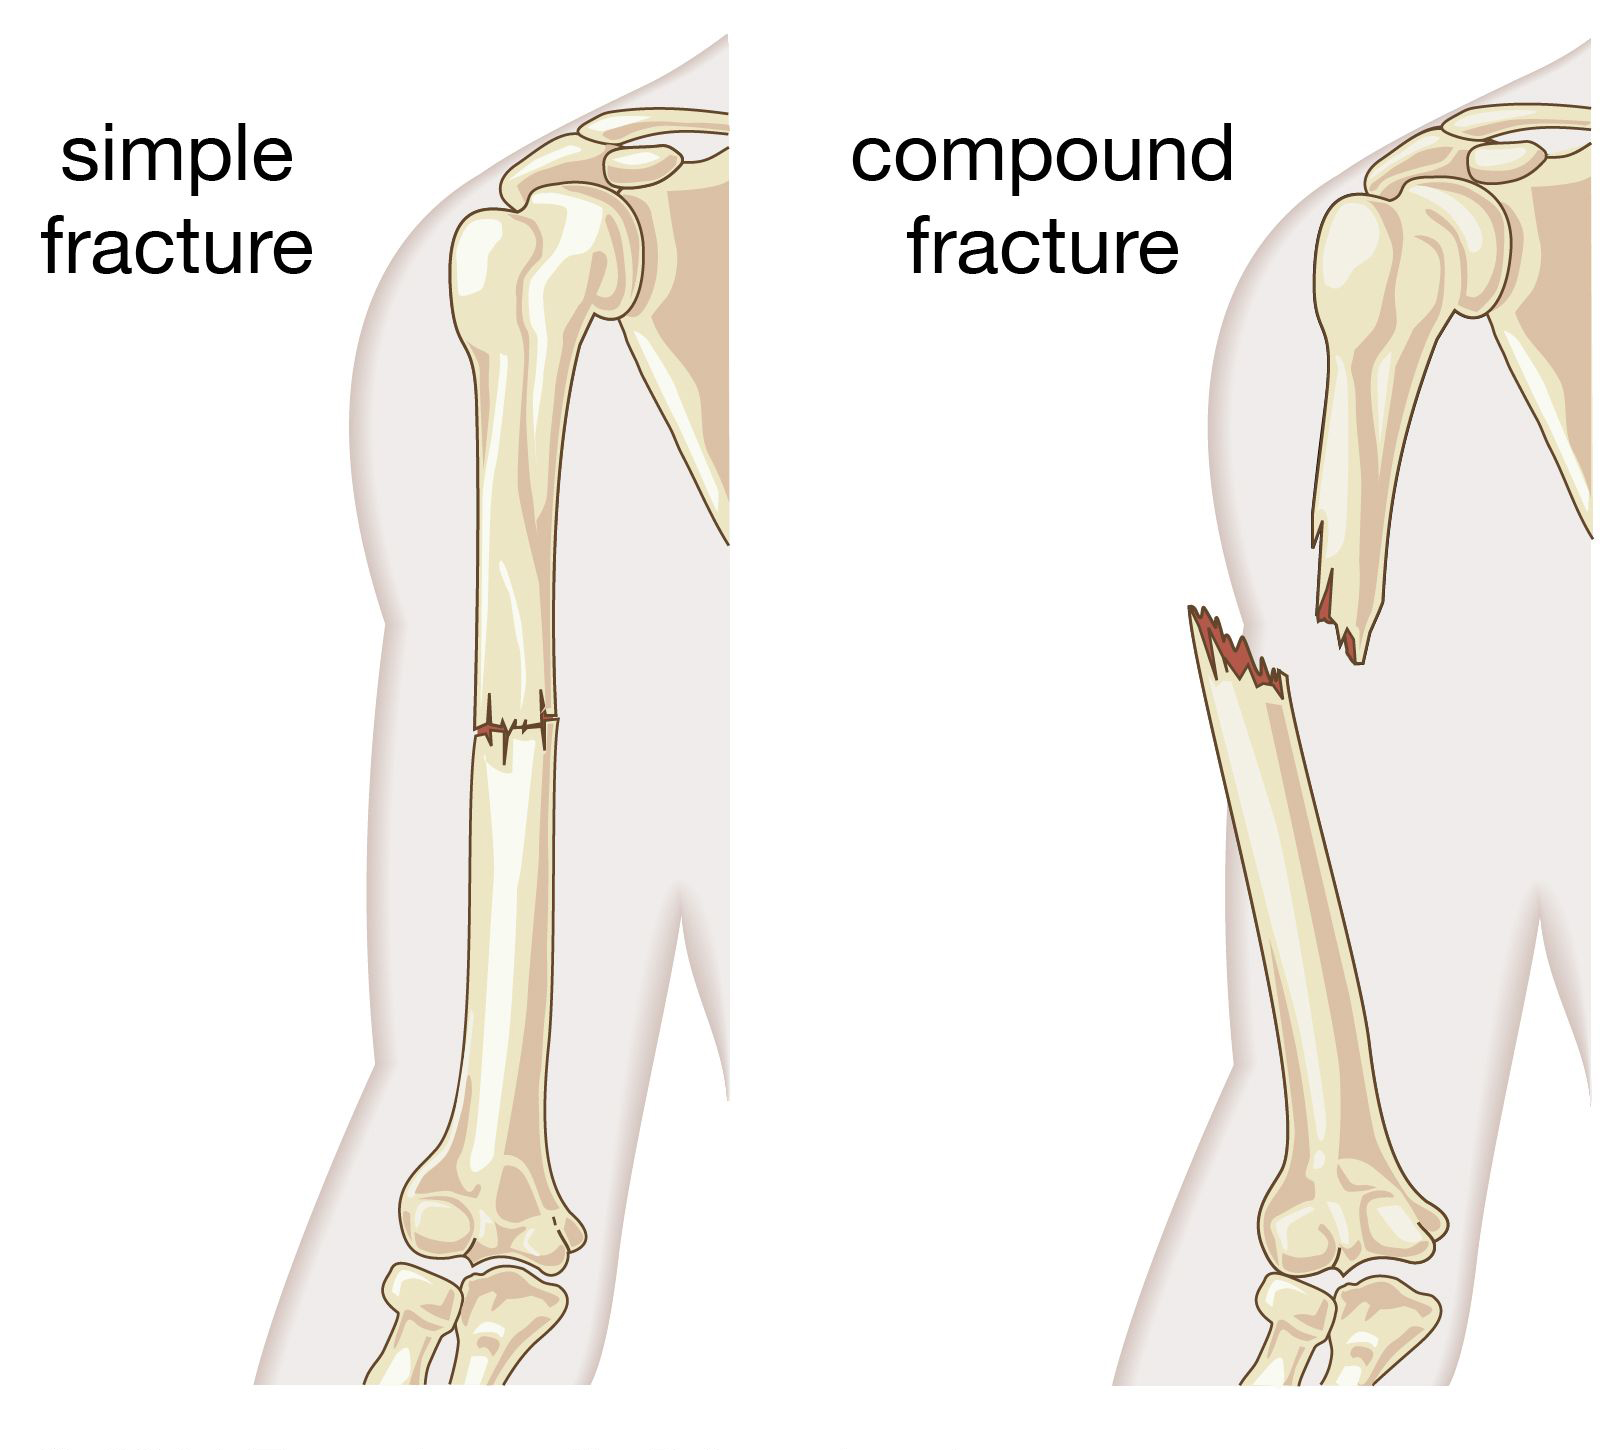

A fracture refers to a break in the bone, which can range from a small crack to a complete break. Fractures are caused by excessive force applied to the bone, either due to accidents, falls, or medical conditions like osteoporosis that weaken the bones.

Simple Fracture

Accidents often lead to fractures, which are breaks in the bone caused by falls, accidents, or trauma. We specialize in the treatment of both simple and compound fractures, ensuring effective healing with minimal discomfort.